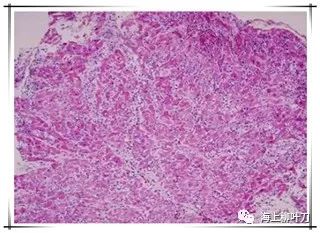

6.這是她的心肌病理切片,放大了100倍。

7.100倍還不是看得很清楚,放大400倍就很明顯了,一個個藍點就是淋巴球。這是很厲害的猛暴性心肌炎,整個心臟都被淋巴球浸潤了。